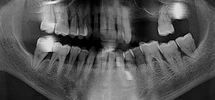

Ortodonti, estetik diş hekimliği, implantoloji ve pedodonti dallarında yoğunlukla çalışmaktayım aynı zamanda "Dişlerim ve Ben" adlı çocuk kitabını yazdım.

Uzmanlık alanları

Diş hekimi